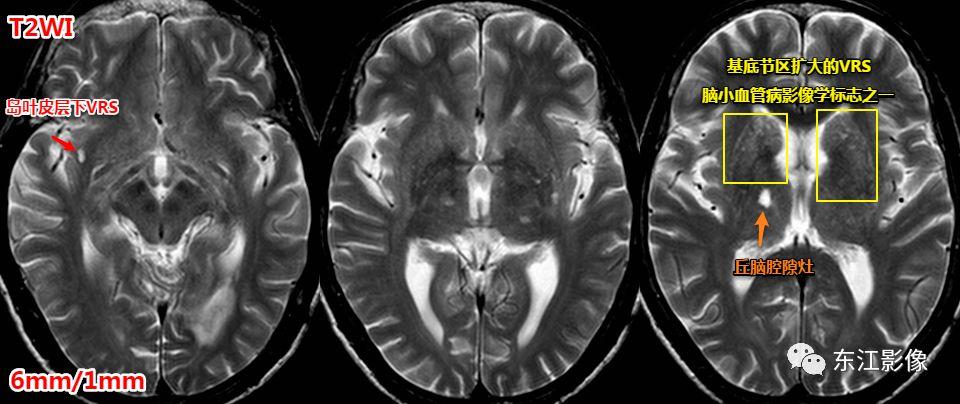

注意,扩大的血管周围间隙也是脑小血管病的影像学标志之一,但并非所有扩大的血管周围间隙均与脑小血管病有联系。

一般认为,基底节区中上区域扩大的血管周围间隙多与脑小血管病有关系。

基底节区扩大的血管周围间隙,丘脑腔隙灶典型影像,均为脑小血管病影像学标志。